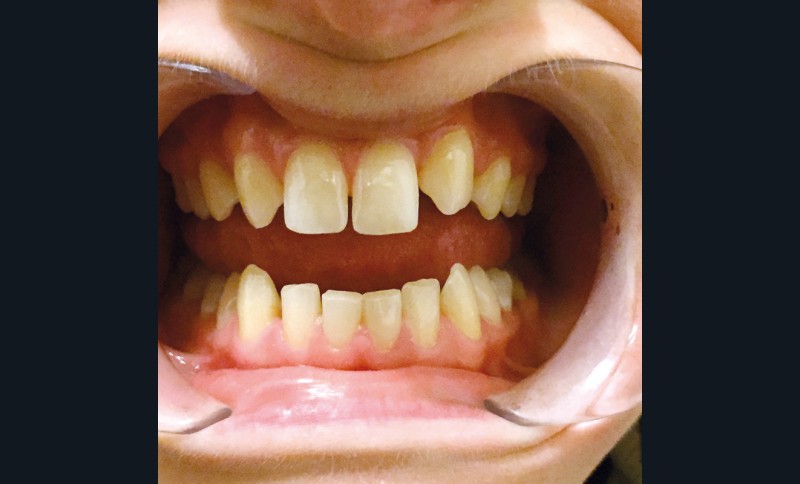

Ce sujet sera abordé par René Serfaty, MCU-PH, responsable du DU Esthétique du sourire à Strasbourg. Aujourd’hui, nous avons les possibilités techniques de réaliser des composites stratifiés de haute qualité. La question reste de maîtriser ces techniques et de les réaliser avec les contraintes économiques d’un cabinet libéral. René Serfaty a donc accepté de relever le challenge : rendre accessible ces techniques grâce à une approche simplifiée de stratification en deux couches. Le résultat permet à l’adolescent de retrouver un confort immédiat aussi bien pour restaurer un angle fracturé que pour maquiller une incisive rhyziforme (fig. 3).